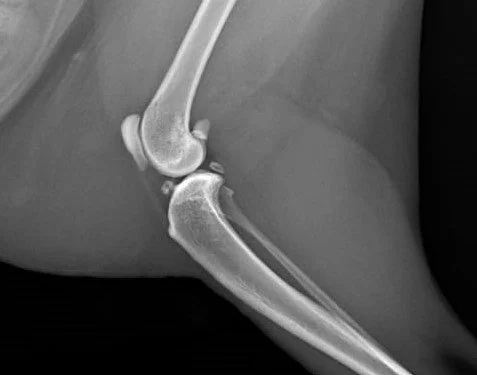

ML view of a feline stifle: Intra-articular soft tissue thickening (compatible with infra-patellar fat pad mineralization)

Unfortunately most clinicians lack the experience of regularly looking at articular radiographs of cats and recognizing abnormalities. In the dog, the presence of osteophytes is the key radiographic feature of OA, but in the feline patient these can be difficult to identify or even absent. It is not unusual to see soft tissue mineralization within feline arthritic joints. Soft tissue thickening and synovial effusion can be evaluated by radiography but are less apparent in feline OA than in other species.